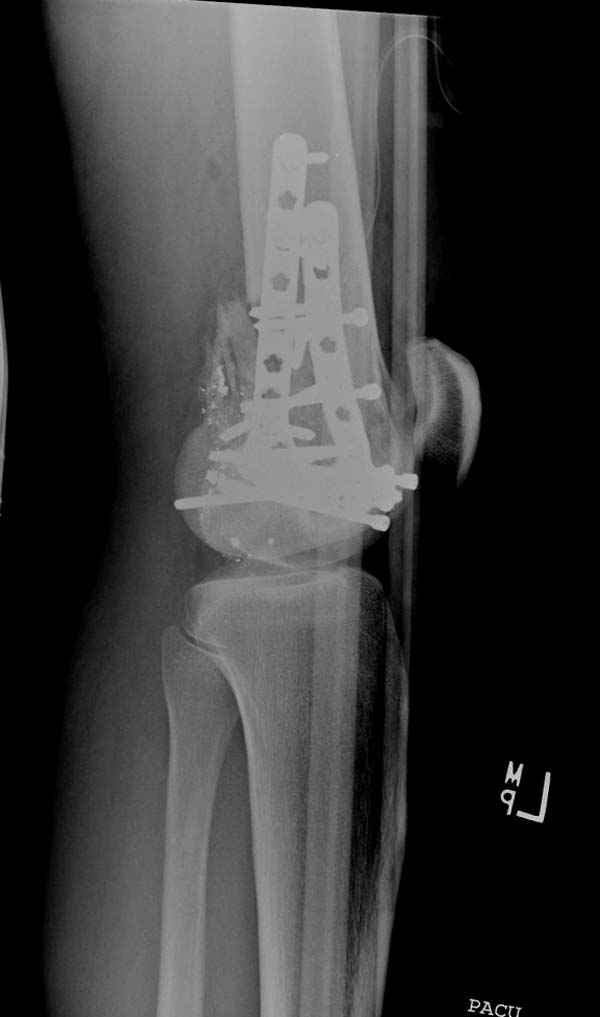

Красиво и быстро?! - две пластины + 18 шурупов.

Идеальная репозиция?! -На снимочке A-P проeкции видна "зазубрина" по суставной поверхности, латеральный снимок - тоже не идеально.

Множество мелких FB в кости.

Выписан через 3 дня после операции - как минимум,надо 7 дней i.v. антибиотикотерапию.